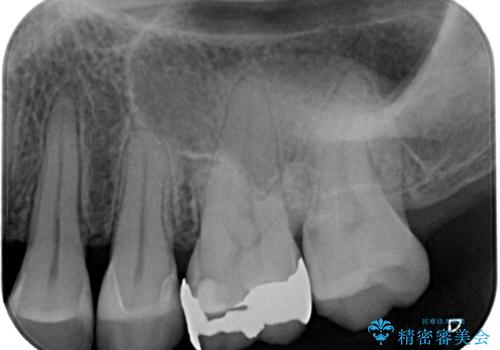

銀歯がとれた セラミックインレー修復

- 銀歯が取れたとのことで来院された患者様です。患者様の歯をあまり削りたくないというご希望に添い、セラミックインレーにて治療を行うこととなりました。

拡大鏡視野下で、保険のプラスチック、虫歯の除去を行い、セラミックインレーに適した形に整えました。

歯と歯茎の間に圧排糸と言われる糸を入れてシリコーン印象材にて精密な型どりをしました。

セラミックインレーの装着時には、唾液の侵入を防ぐために、ラバーダム防湿を行いました。